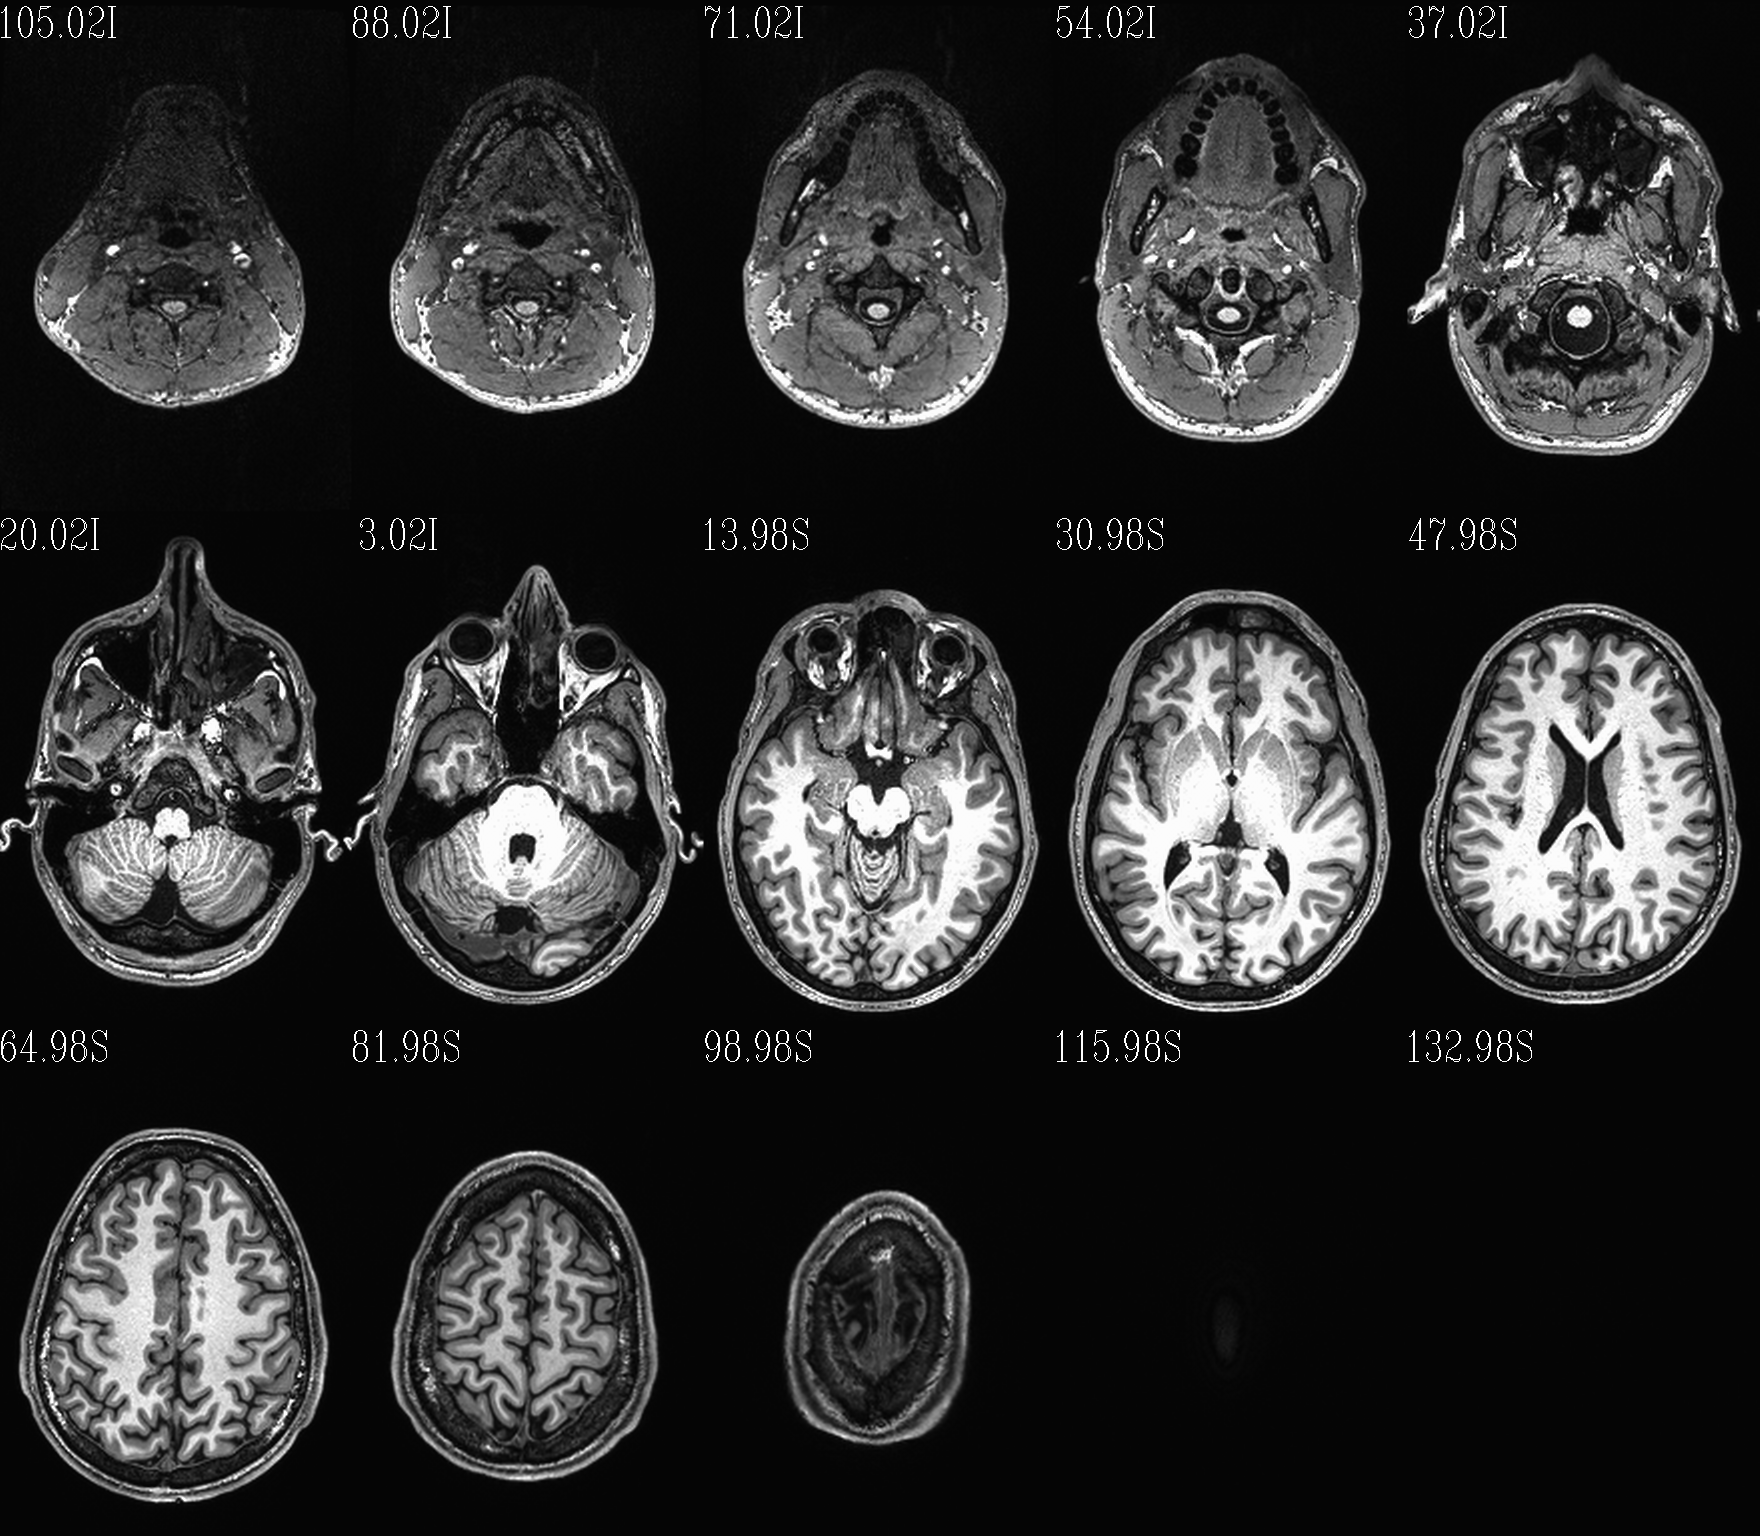

t1w__qc00_anat.*.png |

autoimages, multiple slices per DWI volume, with single scaling across the volume |

Note

Notice that here the T2w volume is really quite oblique to the acquired field of view (FOV). When using this as a reference volume in TORTOISE, the DWI volumes would also end up with major axes unaligned to those of the dset FOV; this would be highly non-ideal for things like RGB coloration and systematic viewing/comparisons. This is dealt with in the next step (“axialization”).